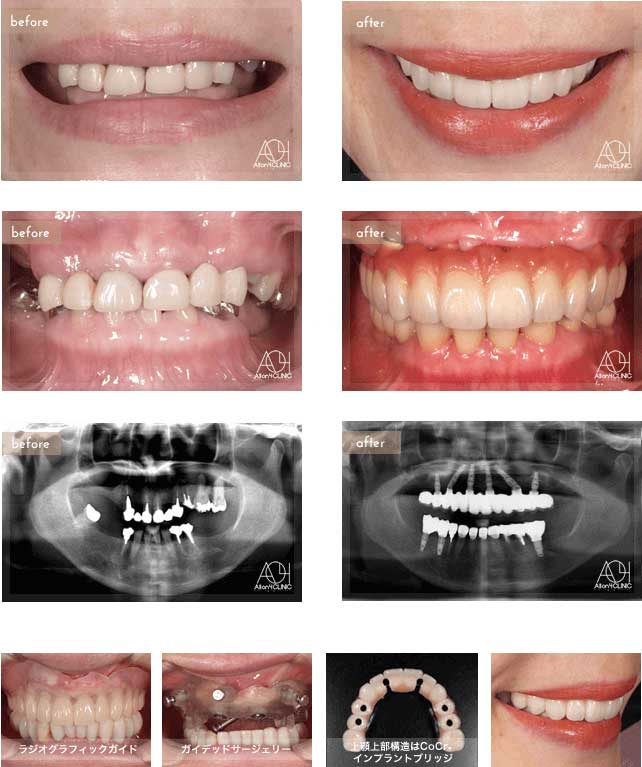

Treatment : All-on-4 zygoma

- Upper All-on-4

- Lower All-on-4

Age : 65 Sex : 男 H.M

| 主訴 | 日本各地のクリニックを受診し、カウンセリングを何回も受けているがどのクリニックで治療を受けるべきか迷っている。 |

| 治療内容 | ガイデッドサージェリーにてインプラント埋入。骨量が少量であったためザイゴマインプラントにて治療 |

| 治療費(総額) | ¥5,200,000(税抜) 『モニター割引適用』 『オリジナル動画撮影協力あり』 |

| リスク | 治療後の口腔管理が不適切な場合、埋入したインプラント周囲に感染・炎症を起こし、脱落する可能性がございます。 |